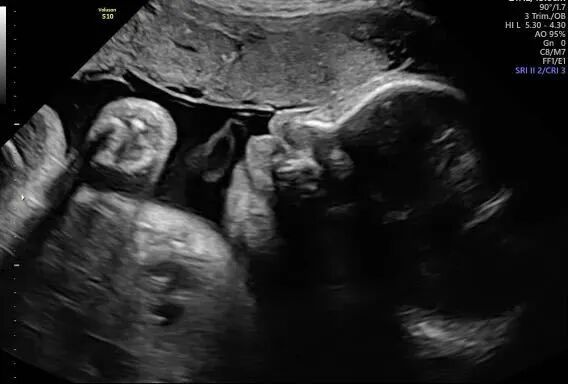

宝宝接近四个月的时候,爱妈Y再次进行了B超检查,此次检查清晰显示出一个健康可爱的女宝宝。爱妈随即将B超照片发送给准妈妈,并满心欢喜地赞叹宝宝的可爱。看到宝宝健康成长,准妈妈既感动又高兴,对爱妈的细心照料表示深深的感激。 准父母成功匹配后,我们会为双方建立一个交流群,这样准父母和爱妈可以方便地进行沟通。在这个群里,爱妈和我们的客服团队会定期更新检查结果和宝宝的成长情况。我们都非常期待下次见到宝宝的时刻!